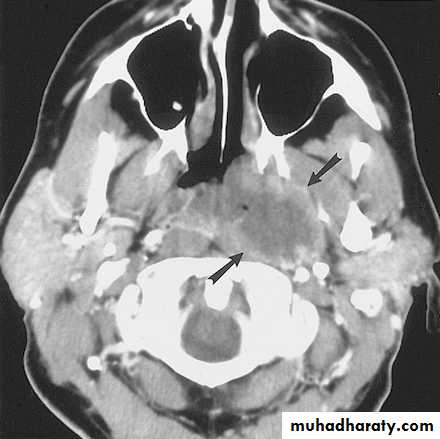

Computed Tomography

Distinguish cystic from solidExtent of lesion

Vascularity (with contrast)

Detection of unknown primary (metastatic)

Pathologic node (lucent, >1.5cm, loss of shape)

Avoid contrast in thyroid lesions

14

15